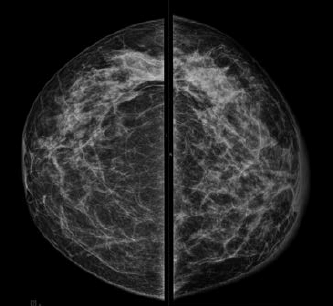

Assinale a alternativa que apresenta corretamente o que observa-se na análise das imagens da mamografia.

Uma paciente de 46 anos realizou esta mamografia.

Assinale a alternativa que contém a descrição e a classificação BIRADS correspondente.